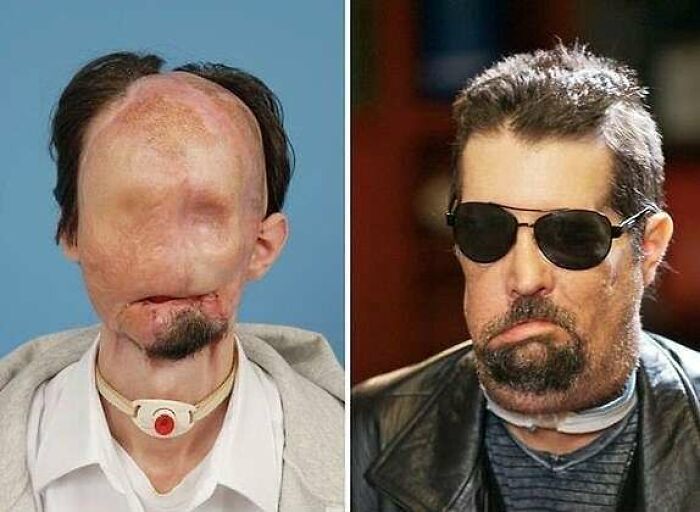

#6 Keď mal Dallas Wiens niečo po dvadsiatke, maľoval vonkajšiu stenu kostola, keď narazil hlavou do drôtu vysokého napätia.

#10 26-ročný pacient po transplantácii odhaľuje svoju novú tvár